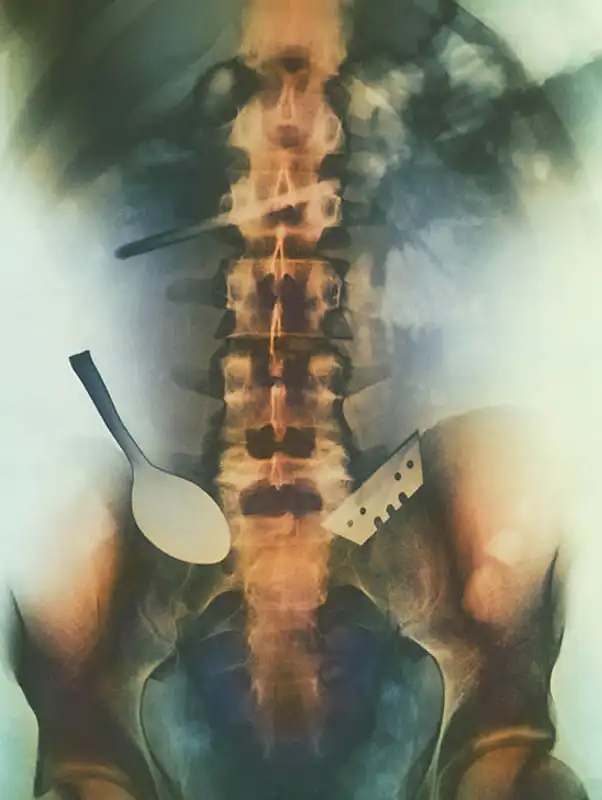

Цветной снимок предметов, которые проглотил пациент, и которые застряли в его кишечнике, включая ложку и лезвие.

Цветной рентген желудка пациента, который проглотил бритву (по центру слева) и лезвия (вверху справа).